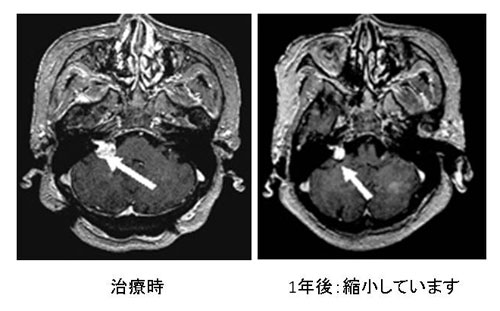

聴神経腫瘍

最大径が2.5cm以下で、何らかの理由(高齢者、全身状態が不良、手術治療がどうしても納得できない場合など)で、手術が不可能な場合が適応になります。ガンマナイフ治療後10年間で90%の確率で腫瘍の成長が止まるか、腫瘍が縮小することが知られています。ただ現在のガンマナイフ治療が確立されてまだ20年程度しか経過していないため、その後の経過は不明な点もあります。また、10%の方はガンマナイフ治療を行っても腫瘍が増大したり、嚢胞を形成したりして脳を圧迫し手術が必要になります。また、治療後頭の中に髄液という水がたまって(水頭症といい自然の経過でもおきます)、簡単な手術(シャント手術)が必要になることがあります。